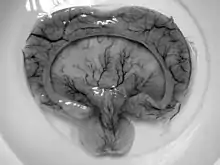

| Gross pathology specimen from a case of alobar holoprosencephaly, a clinical manifestation of Young–Madders syndrome first described as a new condition by doctors Young and Madders in 1987. |

Young–Madders syndrome is detectable from the fetal stage of development largely due to the distinctive consequences of holoprosencephaly, a spectrum of defects or malformations of the brain and face. Facial defects which may manifest in the eyes, nose, and upper lip, featuring cyclopia, anosmia, or in the growth of only a single central incisor, and severe overlapping of the bones of the skull.[2][3] Cardiac and in some cases pulmonary deformities are present.[2] Another signature deformity is bilateral polydactyly, and many patients also suffer from hypoplasia and genital deformities.[1]